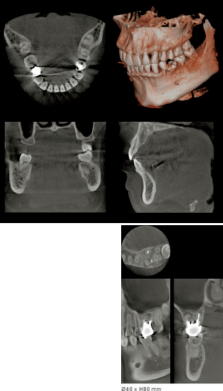

歯科用 デジタルCT 歯科用のデジタルCTです。被曝線量が少なく、安心安全のために断層撮影の上、外科治療やインプラント治療を行えます。また、矯正に必要な特殊なセファロ撮影も行えます。 |